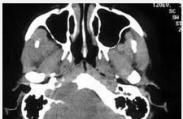

急性硬脑膜外血肿

628健康网为您分享有关急性硬脑膜外血肿的症状,急性硬脑膜外血肿的治疗方法,急性硬脑膜外血肿的预防知识,急性硬脑膜外血...

小儿颅内出血

628健康网为您分享有关小儿颅内出血的症状,小儿颅内出血的治疗方法,小儿颅内出血的预防知识,小儿颅内出血的症状图片,小...

小儿脑脓肿

628健康网为您分享有关小儿脑脓肿的症状,小儿脑脓肿的治疗方法,小儿脑脓肿的预防知识,小儿脑脓肿的症状图片,小儿脑脓肿...